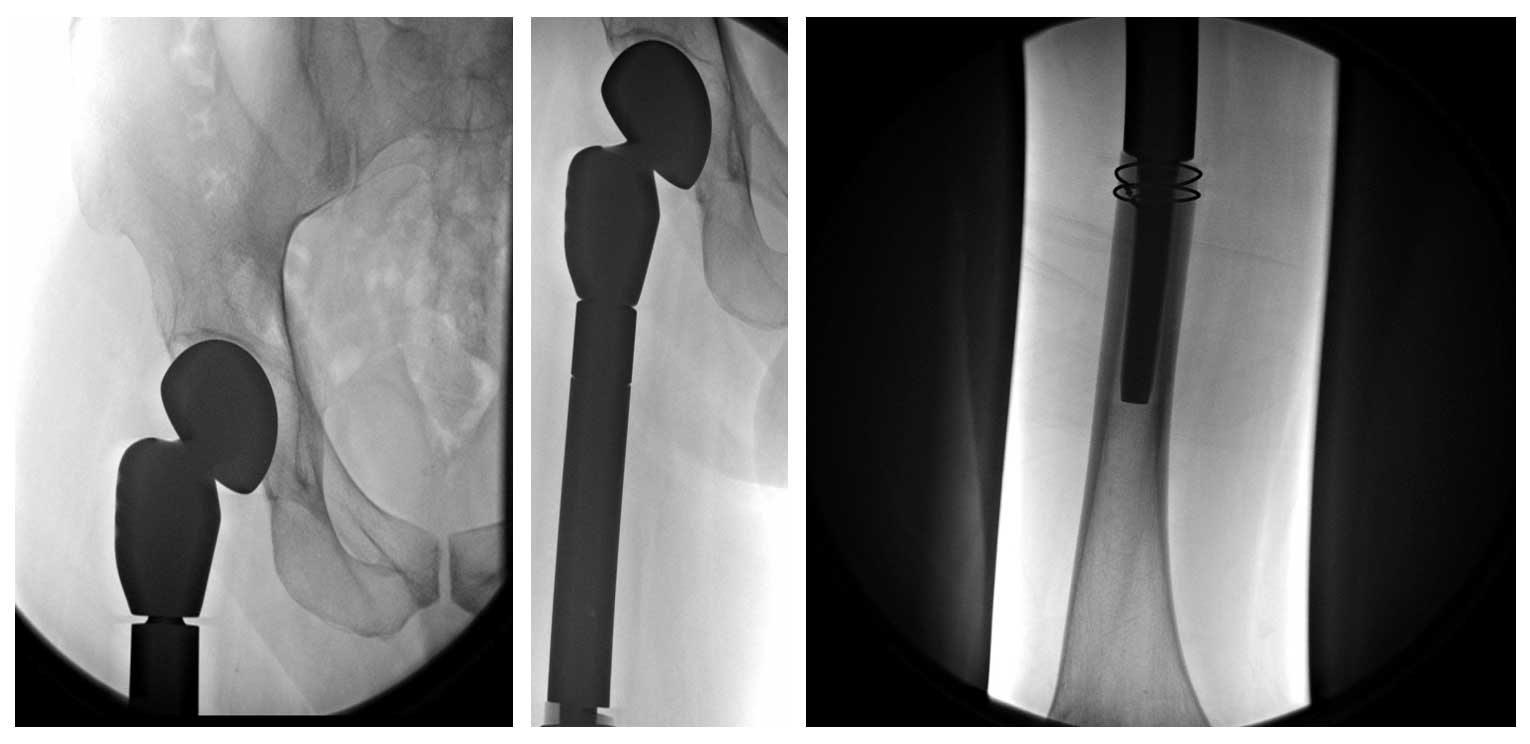

Ameliyat Sonrası: Röntgende rezeksiyon sonrası uygulanan tümör protezi görülmekte.